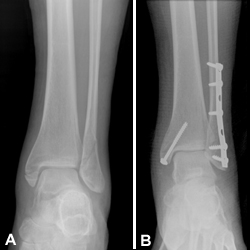

(Left) X-ray of syndesmotic injury with lateral malleolus fracture. Note the space between the tibia and fibula. (Right) Surgical repair.